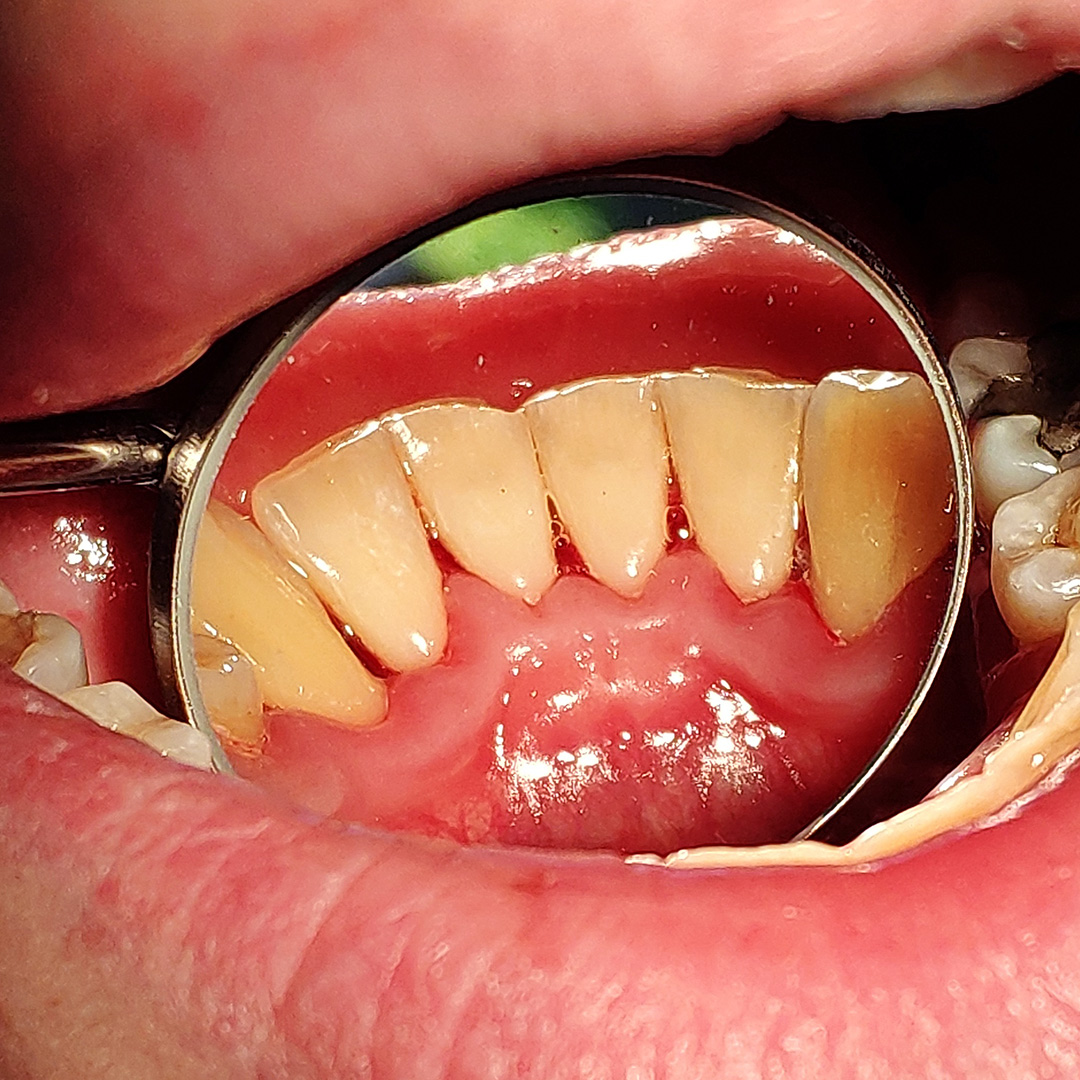

До и после лечения

В ходе процедуры Антоном Алексеевичем были проведены следующие работы:

- удаление над- и поддесневых зубных отложений с помощью ультразвукового аппарата;

- чистка зубов аппаратом Airflow;

- полировка зубов щеткой с пастой "Detartrine Z";

- медикаментозная обработка десны 3% перекисью водорода и 0,05% хлоргексидином;

- даны рекомендации по ежедневной личной гигиене полости рта.